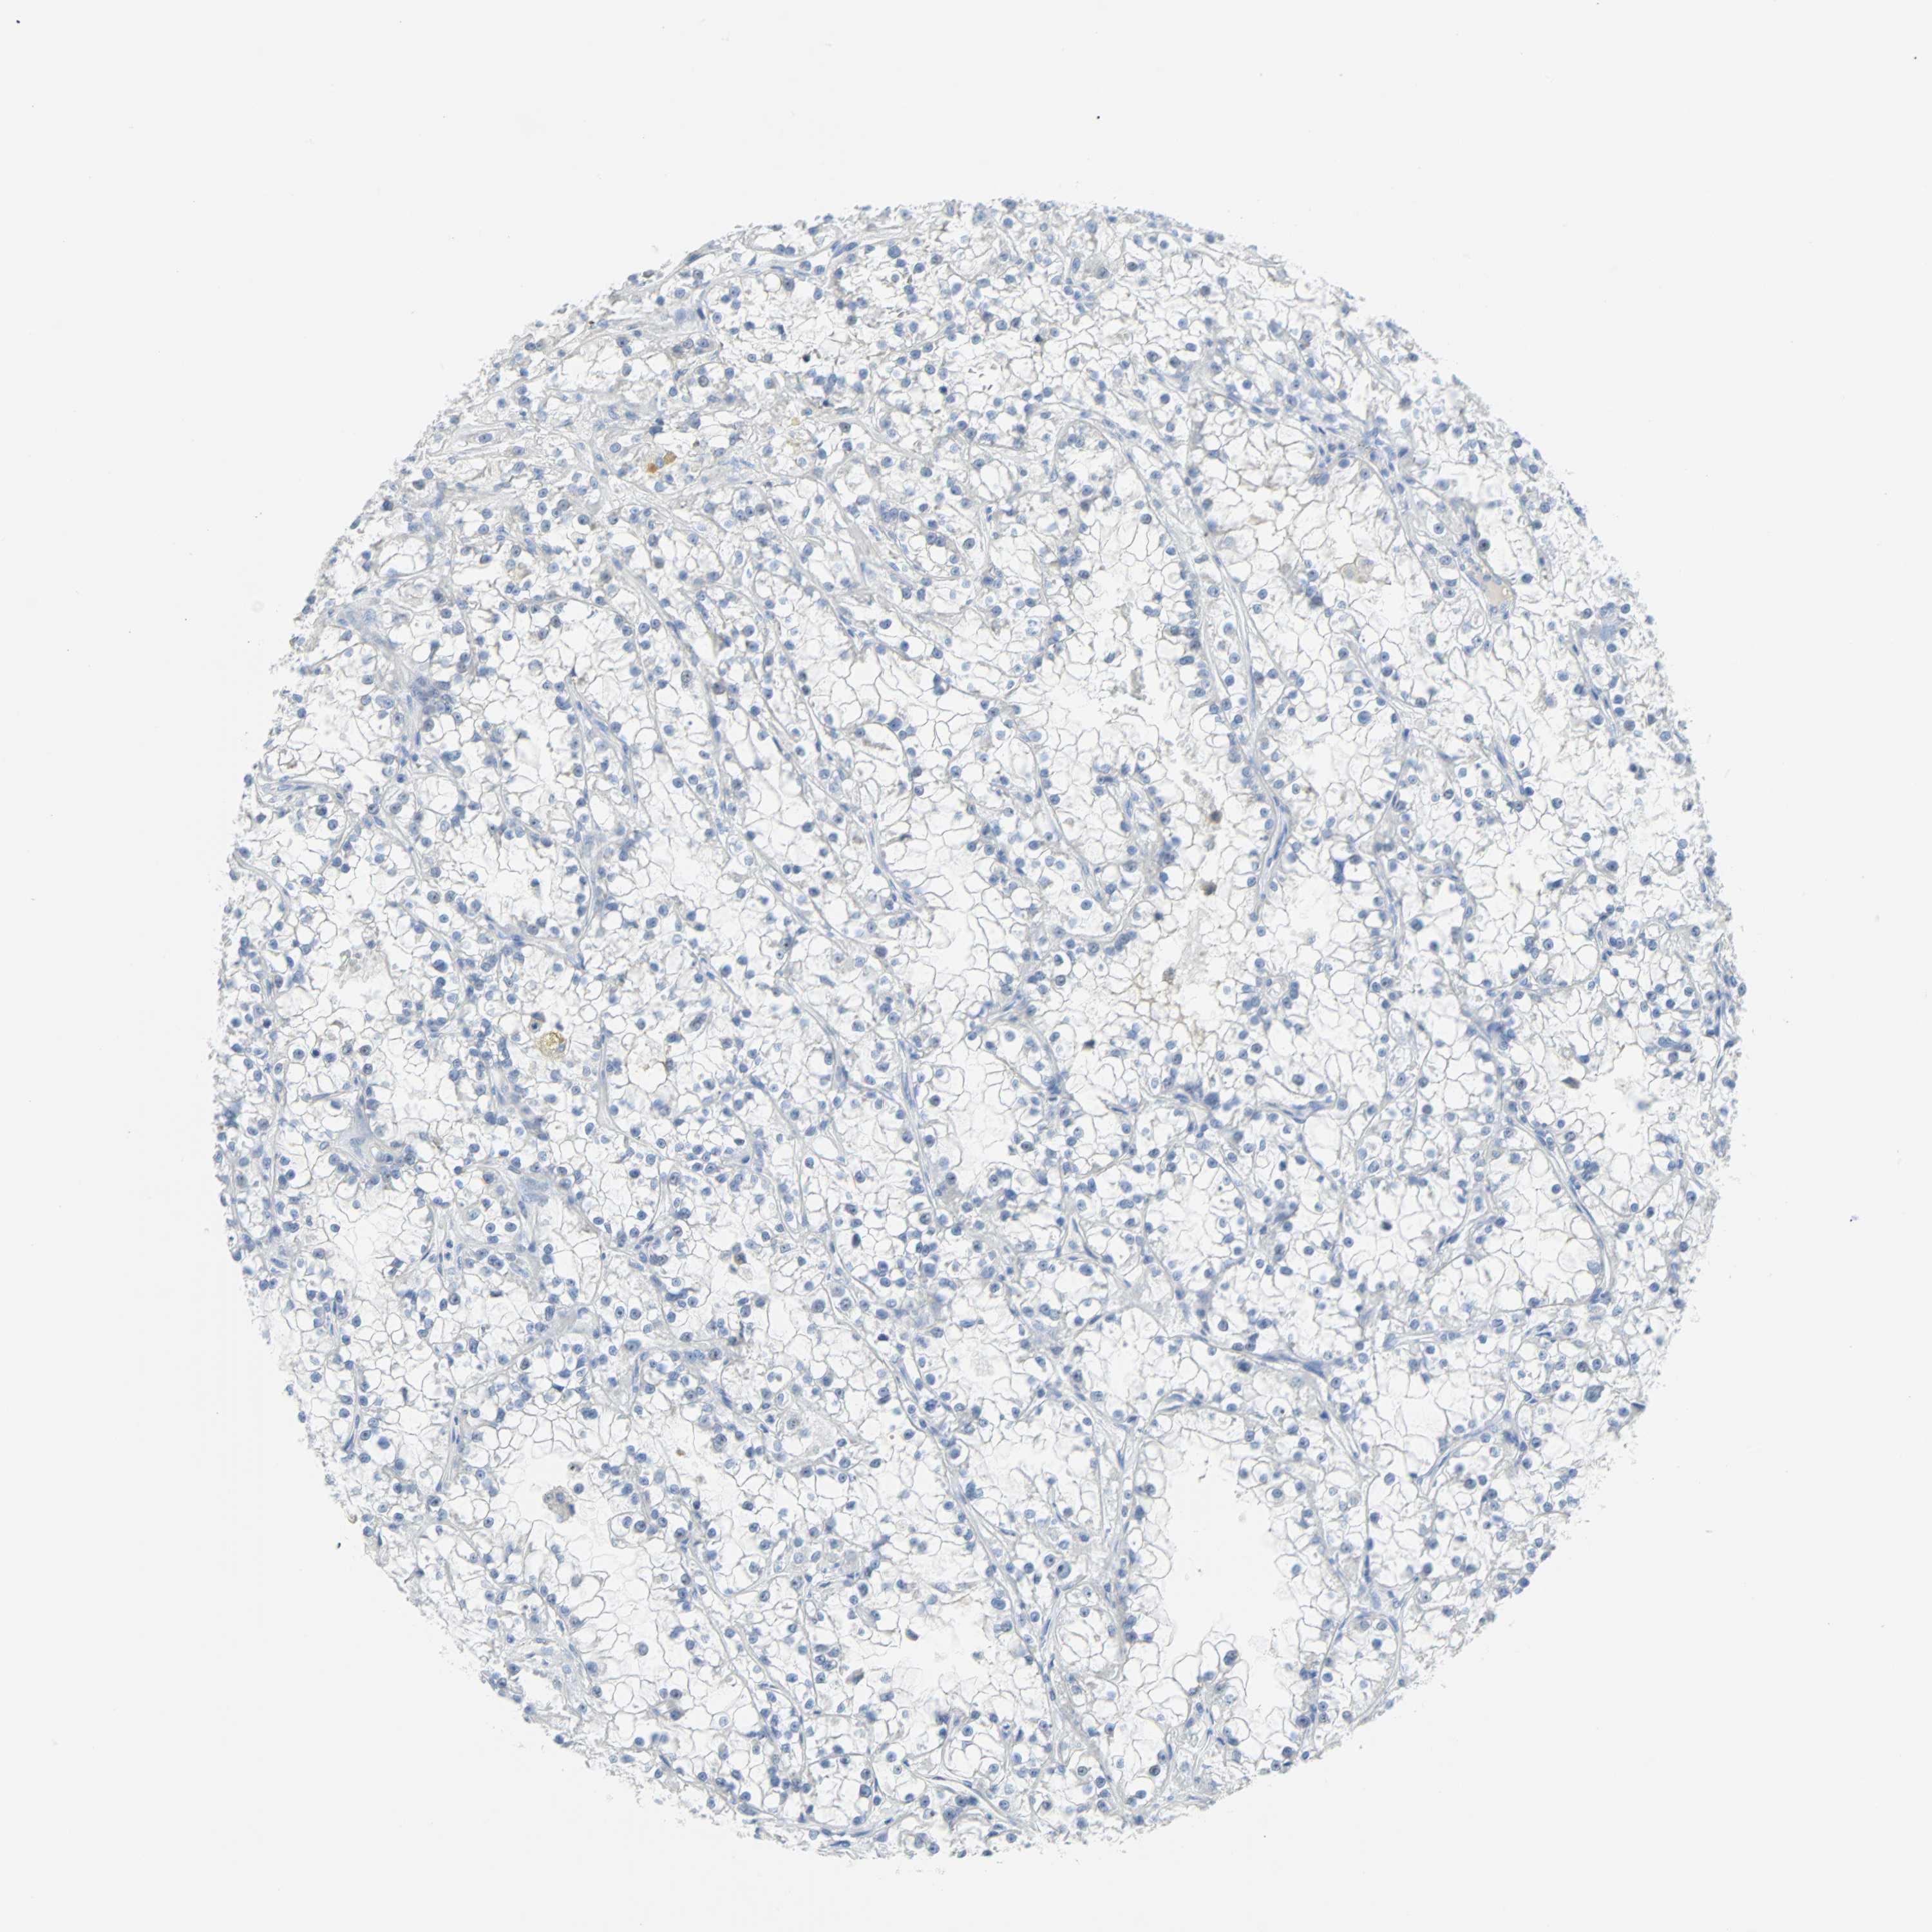

TCGA-UZ-A9PS-01A 62 years, female, black or african american, stage:Stage II, alive, 2167 days 1.8

TCGA-DW-7842-01A 52 years, male, white, stage:Stage I, alive, 92 days 1.8

TCGA-Y8-A897-01A 68 years, female, white, stage:Stage I, alive, 549 days 1.8

TCGA-J7-A8I2-01A 75 years, male, asian, stage:Stage I, alive, 307 days 1.8